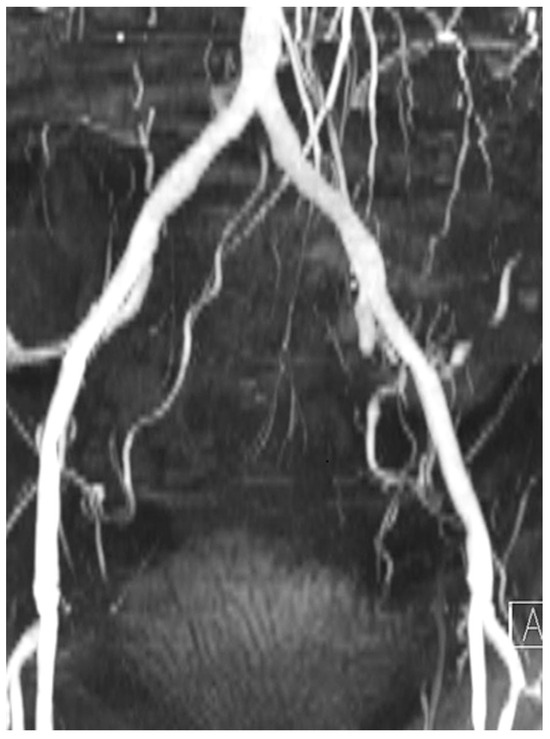

Ischaemic type ECG-modifications are not always correlated to cardiac causes. We present a case of a 63-yearold man with metastatic kidney carcinoma who had ECGabnormalities suspicious for myocardial ischaemia due to a biliary problem, which were com...